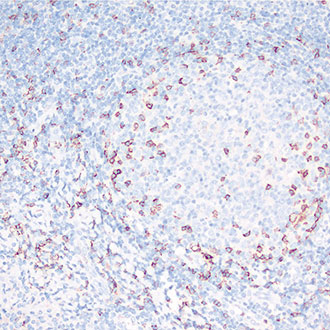

bcl-6

bcl-6 -